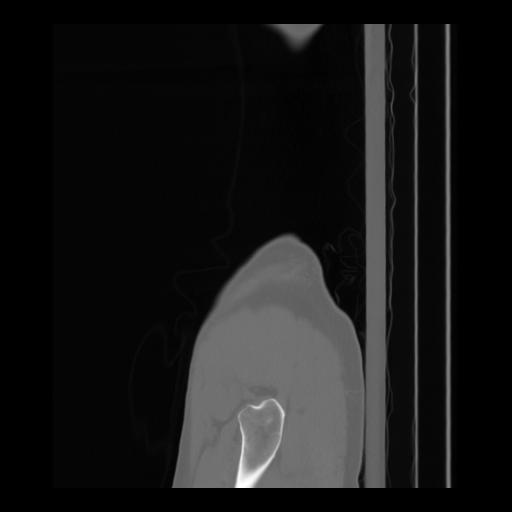

36 CUERPO,CE,Sagittal,3.000,CUERPO,Sagittal,